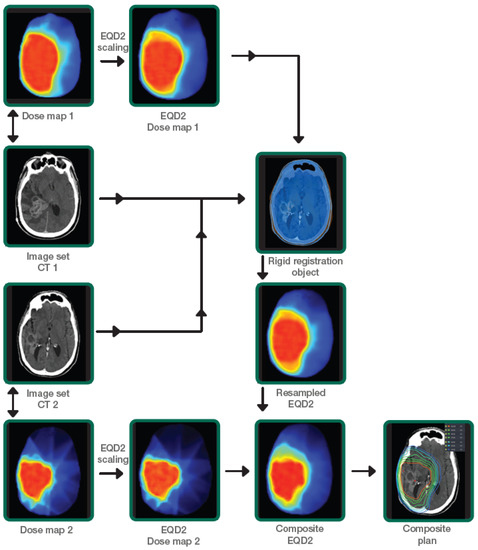

2.3. PRDR Treatment Planning and Delivery